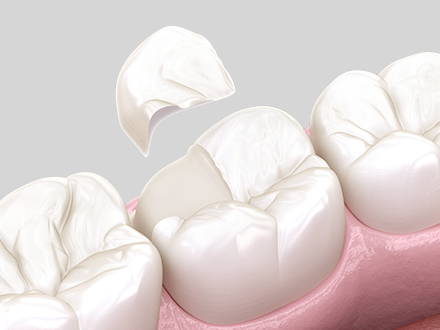

충치로 손상된 부위를 정밀하게 본

만들어 넣는 부분 보철 치료로,

강도와 밀착력이 뛰어납니다.

손상 부위를 본떠 정밀하게 제작하는 맞춤 보철

자연 치아와 유사한 자연스러운 외형

강한 저작력에도 견디는 우수한 내구성

장기간 기능을 유지할 수 있는 안정적인 수명